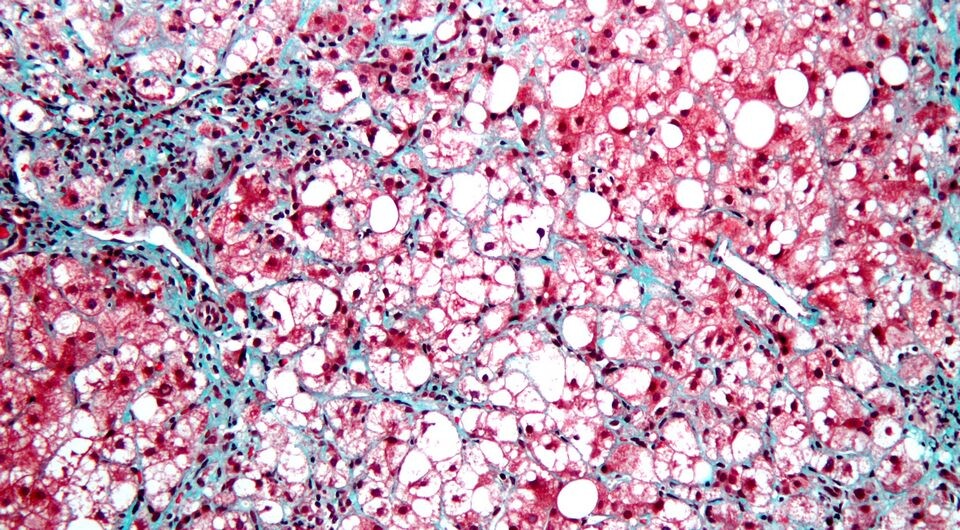

Nephron / Wikimedia Commons / CC-BY-SA-3.0

Стеатогепатит, связанный с метаболической дисфункцией (ССМД, MASH; ранее назывался неалкогольным стеатогепатитом) представляет собой наиболее тяжелую форму жировой болезни печени, связанной с метаболической дисфункцией (МАЖБП, MAFLD; ранее известна как неалкогольная жировая болезнь печени). Патогенез этого заболевания предположительно связан с инсулинорезистентностью и, как следствие, избыточным накоплением жиров в клетках печени, которое приводит к липотоксичности, воспалительному повреждению и далее развитию фиброза и цирроза. Достаточно эффективных методов лечения в клинической практике пока нет. Агонист рецепторов к глюкагоноподобному пептиду-1 (ГПП-1) семаглутид уменьшает инсулинорезистентность и применяется для лечения сахарного диабета и уменьшения массы тела, а также для снижения связанных с этими проблемами сердечно-сосудистых рисков.

Разрешение стеатогепатита без ухудшения фиброза наблюдалось у 62,9 процента пациентов, получавших активный препарат и 34,3 процента — плацебо (p < 0,001), а уменьшение фиброза без усугубления стеатогепатита — у 36,8 против 22,4 процента (p < 0,001). Одновременное разрешение стеатогепатита с уменьшением фиброза произошло у 32,7 процента участников в основной группе против 16,1 процента в контрольной (p < 0,001). Среднее уменьшение массы тела составило 10,5 против 2,0 процента (p < 0,001). Эти показатели не теряли значимости при анализе по подгруппам в соответствии с возрастом, полом, индексом массы тела, наличием сахарного диабета и стадией фиброза печени. Гистологическая динамика сопровождалась улучшением функциональных показателей печени. Нежелательные явления соответствовали известному профилю безопасности семаглутида.